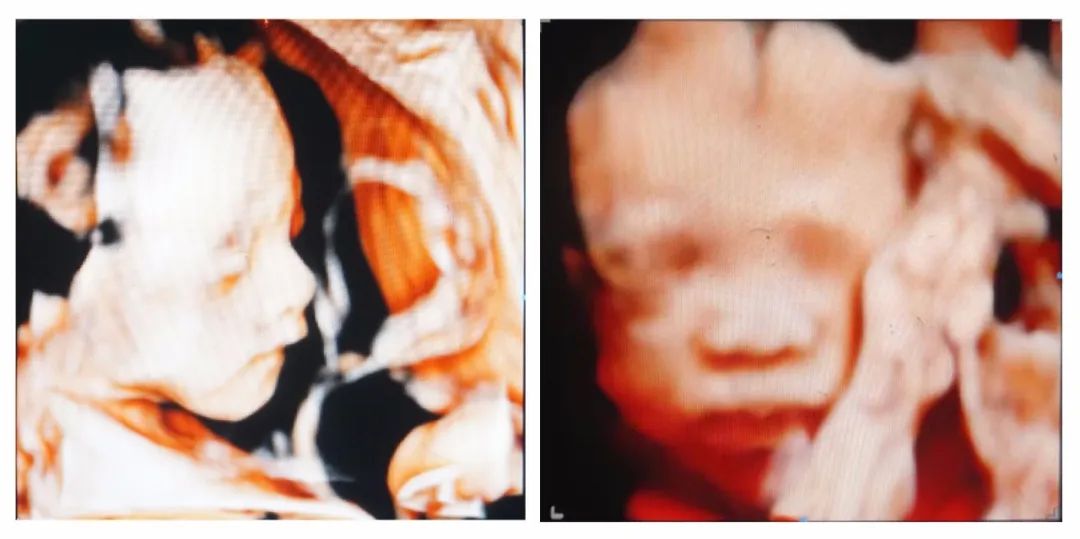

B超、四维彩超显示胎儿畸形

如果B超下显示胎儿有痴呆样面容、指(趾)端畸形、小头、心脏畸形等特征,那么很可能在出生后也伴有不同程度的智力低下。

(图片源自:遂宁妇产医院 侵删)